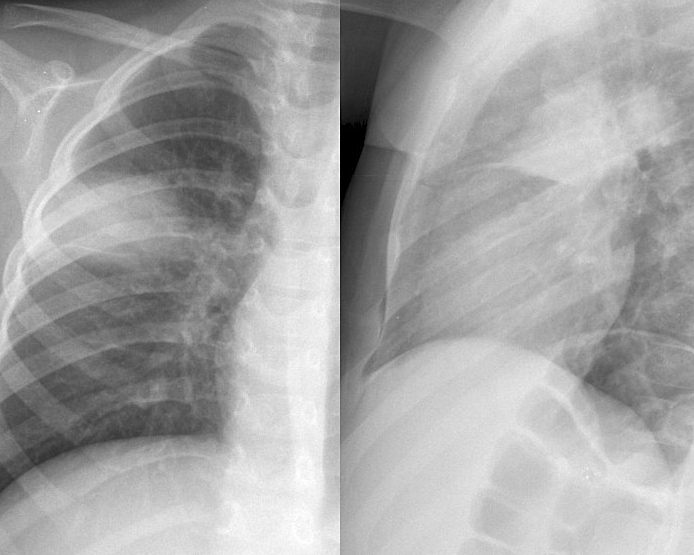

Round pneumonia

different case